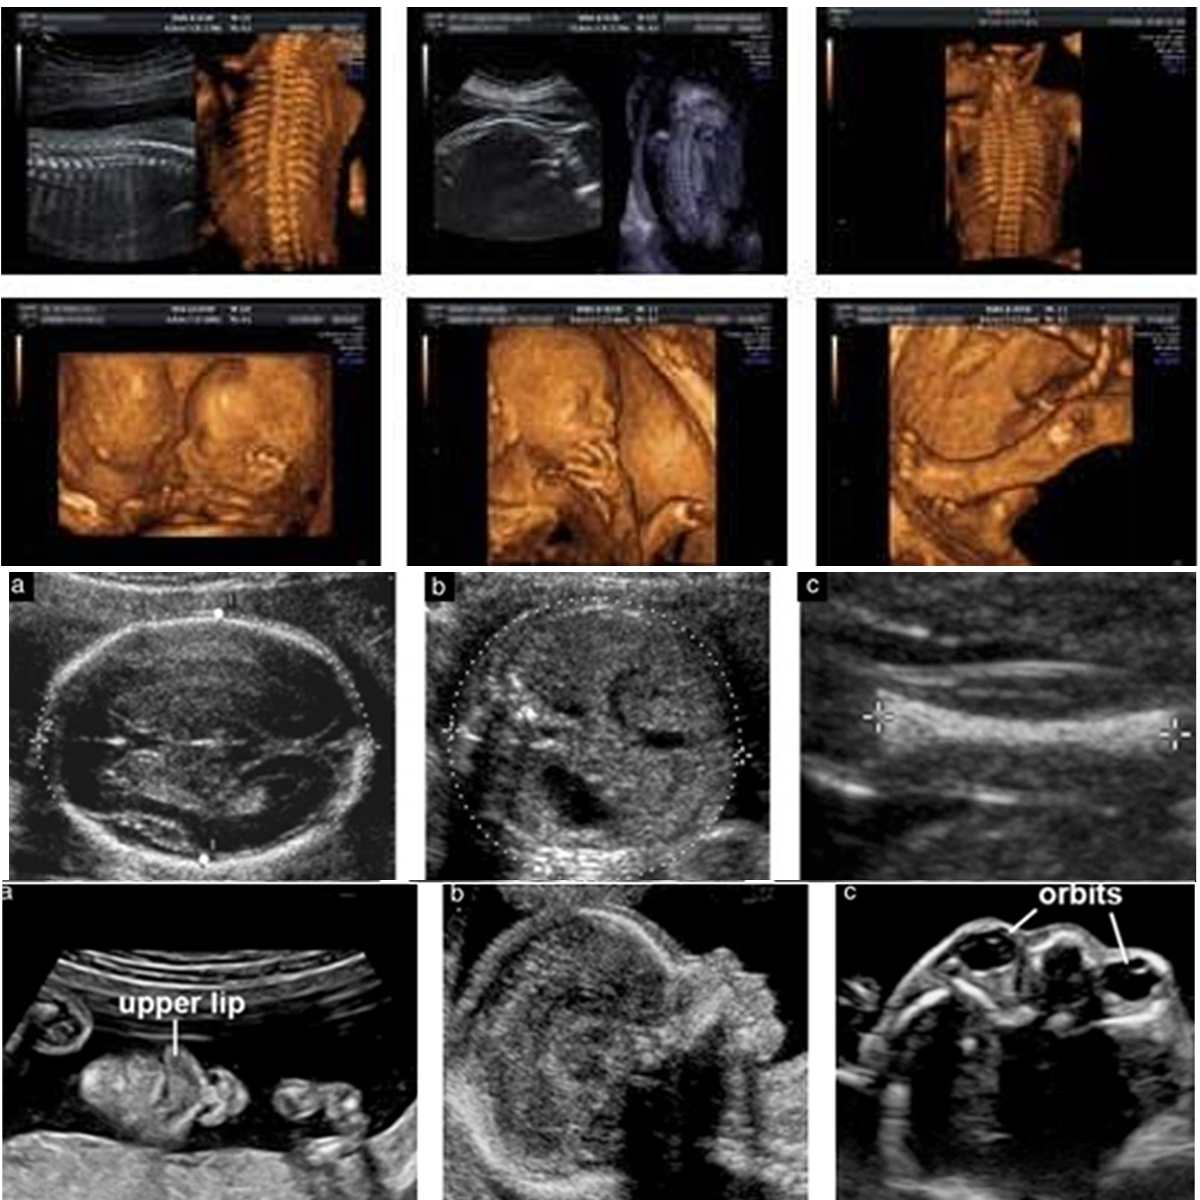

IV. Anomaly Scan / Level II (Done between 20-24 weeks):

Anomaly scan is done at 18-20 weeks of gestation to rule out major structural problems. Fetal growth, amniotic fluid are also checked at the same time. Some patients may need a review scan in case views are not clear due to maternal obesity, previous maternal surgery or at times due to fetal position. Indian MTP law doesn’t allow termination beyond 20 weeks even in case of major malformations and hence it is recommended to do anomaly scan before 20 weeks.

III. Early Anomaly Scan / Risk Reassessment Scan (In case of any structural defects in fetus and high risk on biochemical screening) (Done between 16-18 weeks):

Those who have missed first trimester screening can be offered second trimester screening 16 weeks onwards, which involves a blood test (Quadruple marker test) and ultrasound for fetal growth, structural survey and markers for chromosomal problems.